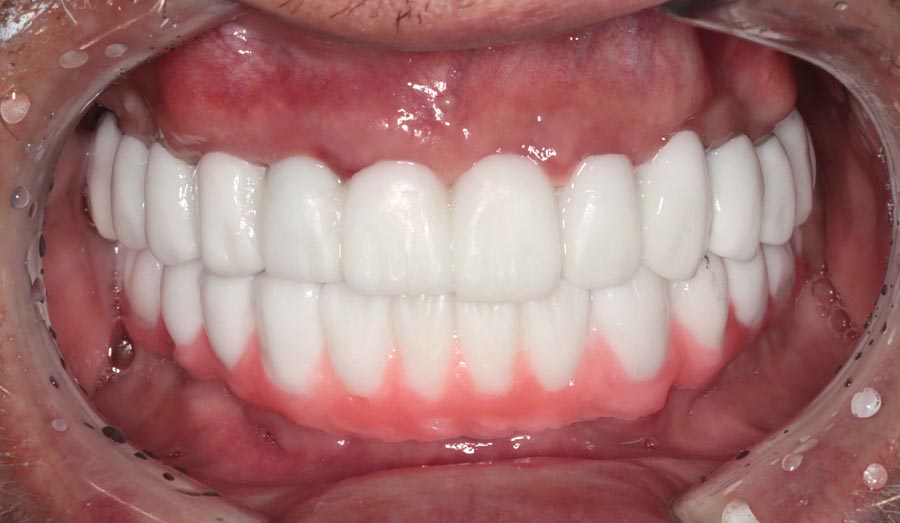

Final prostheses, intraoral, frontal. Homecare is still a problem. The final restorations are much kinder to the tissues and we hope this will resolve some of the inflammation.